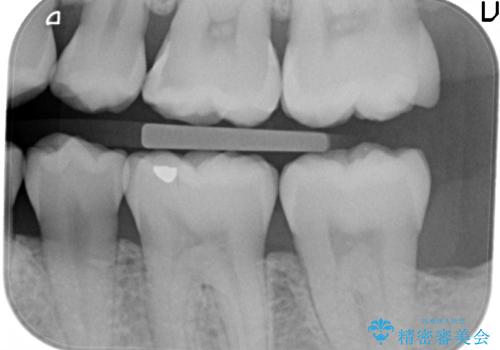

治療前の写真では虫歯はわかりにくいですが、レントゲンではっきり見えます。

虫歯は外の入り口は小さいままで、中で広がっていることが多いため、要注意です。

口の中を目で見てわかるレベルの虫歯ですと、進行してしまっています。

虫歯はレントゲンを取らないと、発見できません。

歯科検診はあくまで余程の状態のスクリーニングですので、きちんとレントゲンを定期的にとって、早期に治療することが重要です。